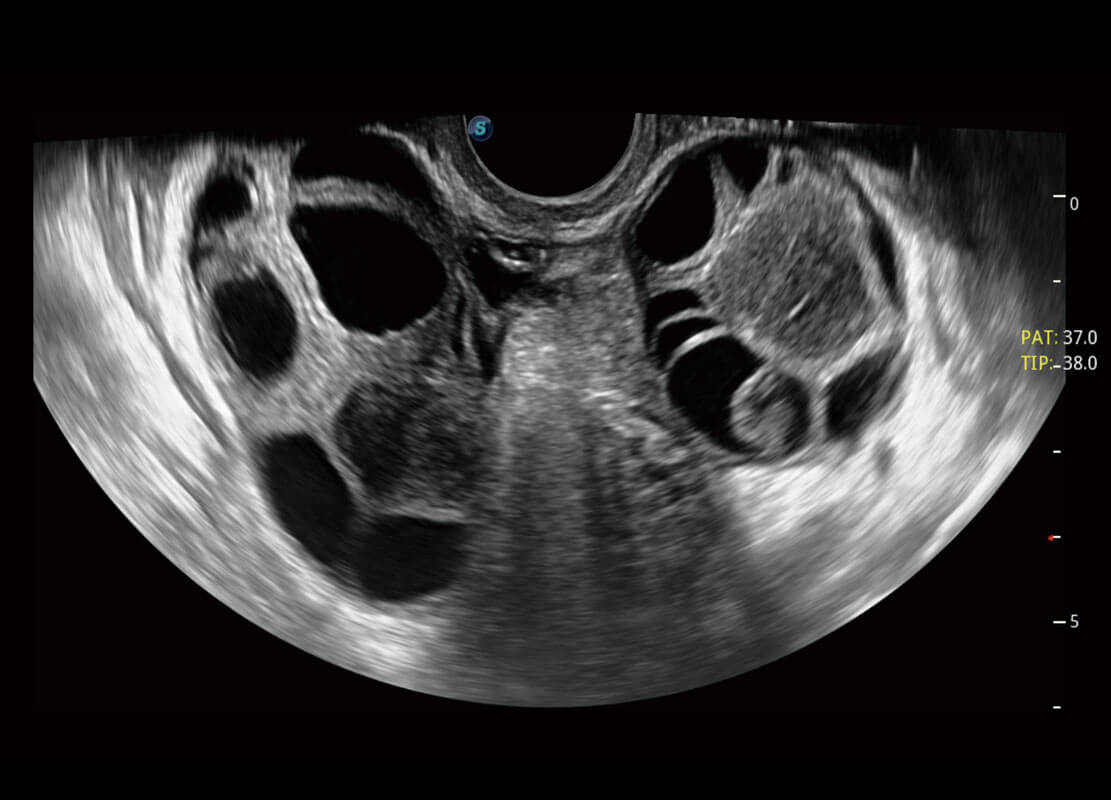

盆底超声

P60为盆底超声检查提供应用方案,多种腔内及腹部容积探头提供从二维、三维到四维的优异图像品质,实时快速三维容积数据获取,专业的测量工具包等人性化设计,为超声医生诊断提供有力保障。

S-Pelvic

能够简化盆底检查的操作流程,可在二维模式及三维成像模式下实现一键自动提取出标准切面、自动识别当前切面、自动测量,提升盆底检查的高效性,同时也能让青年医生快捷的获得准确的检查结果。